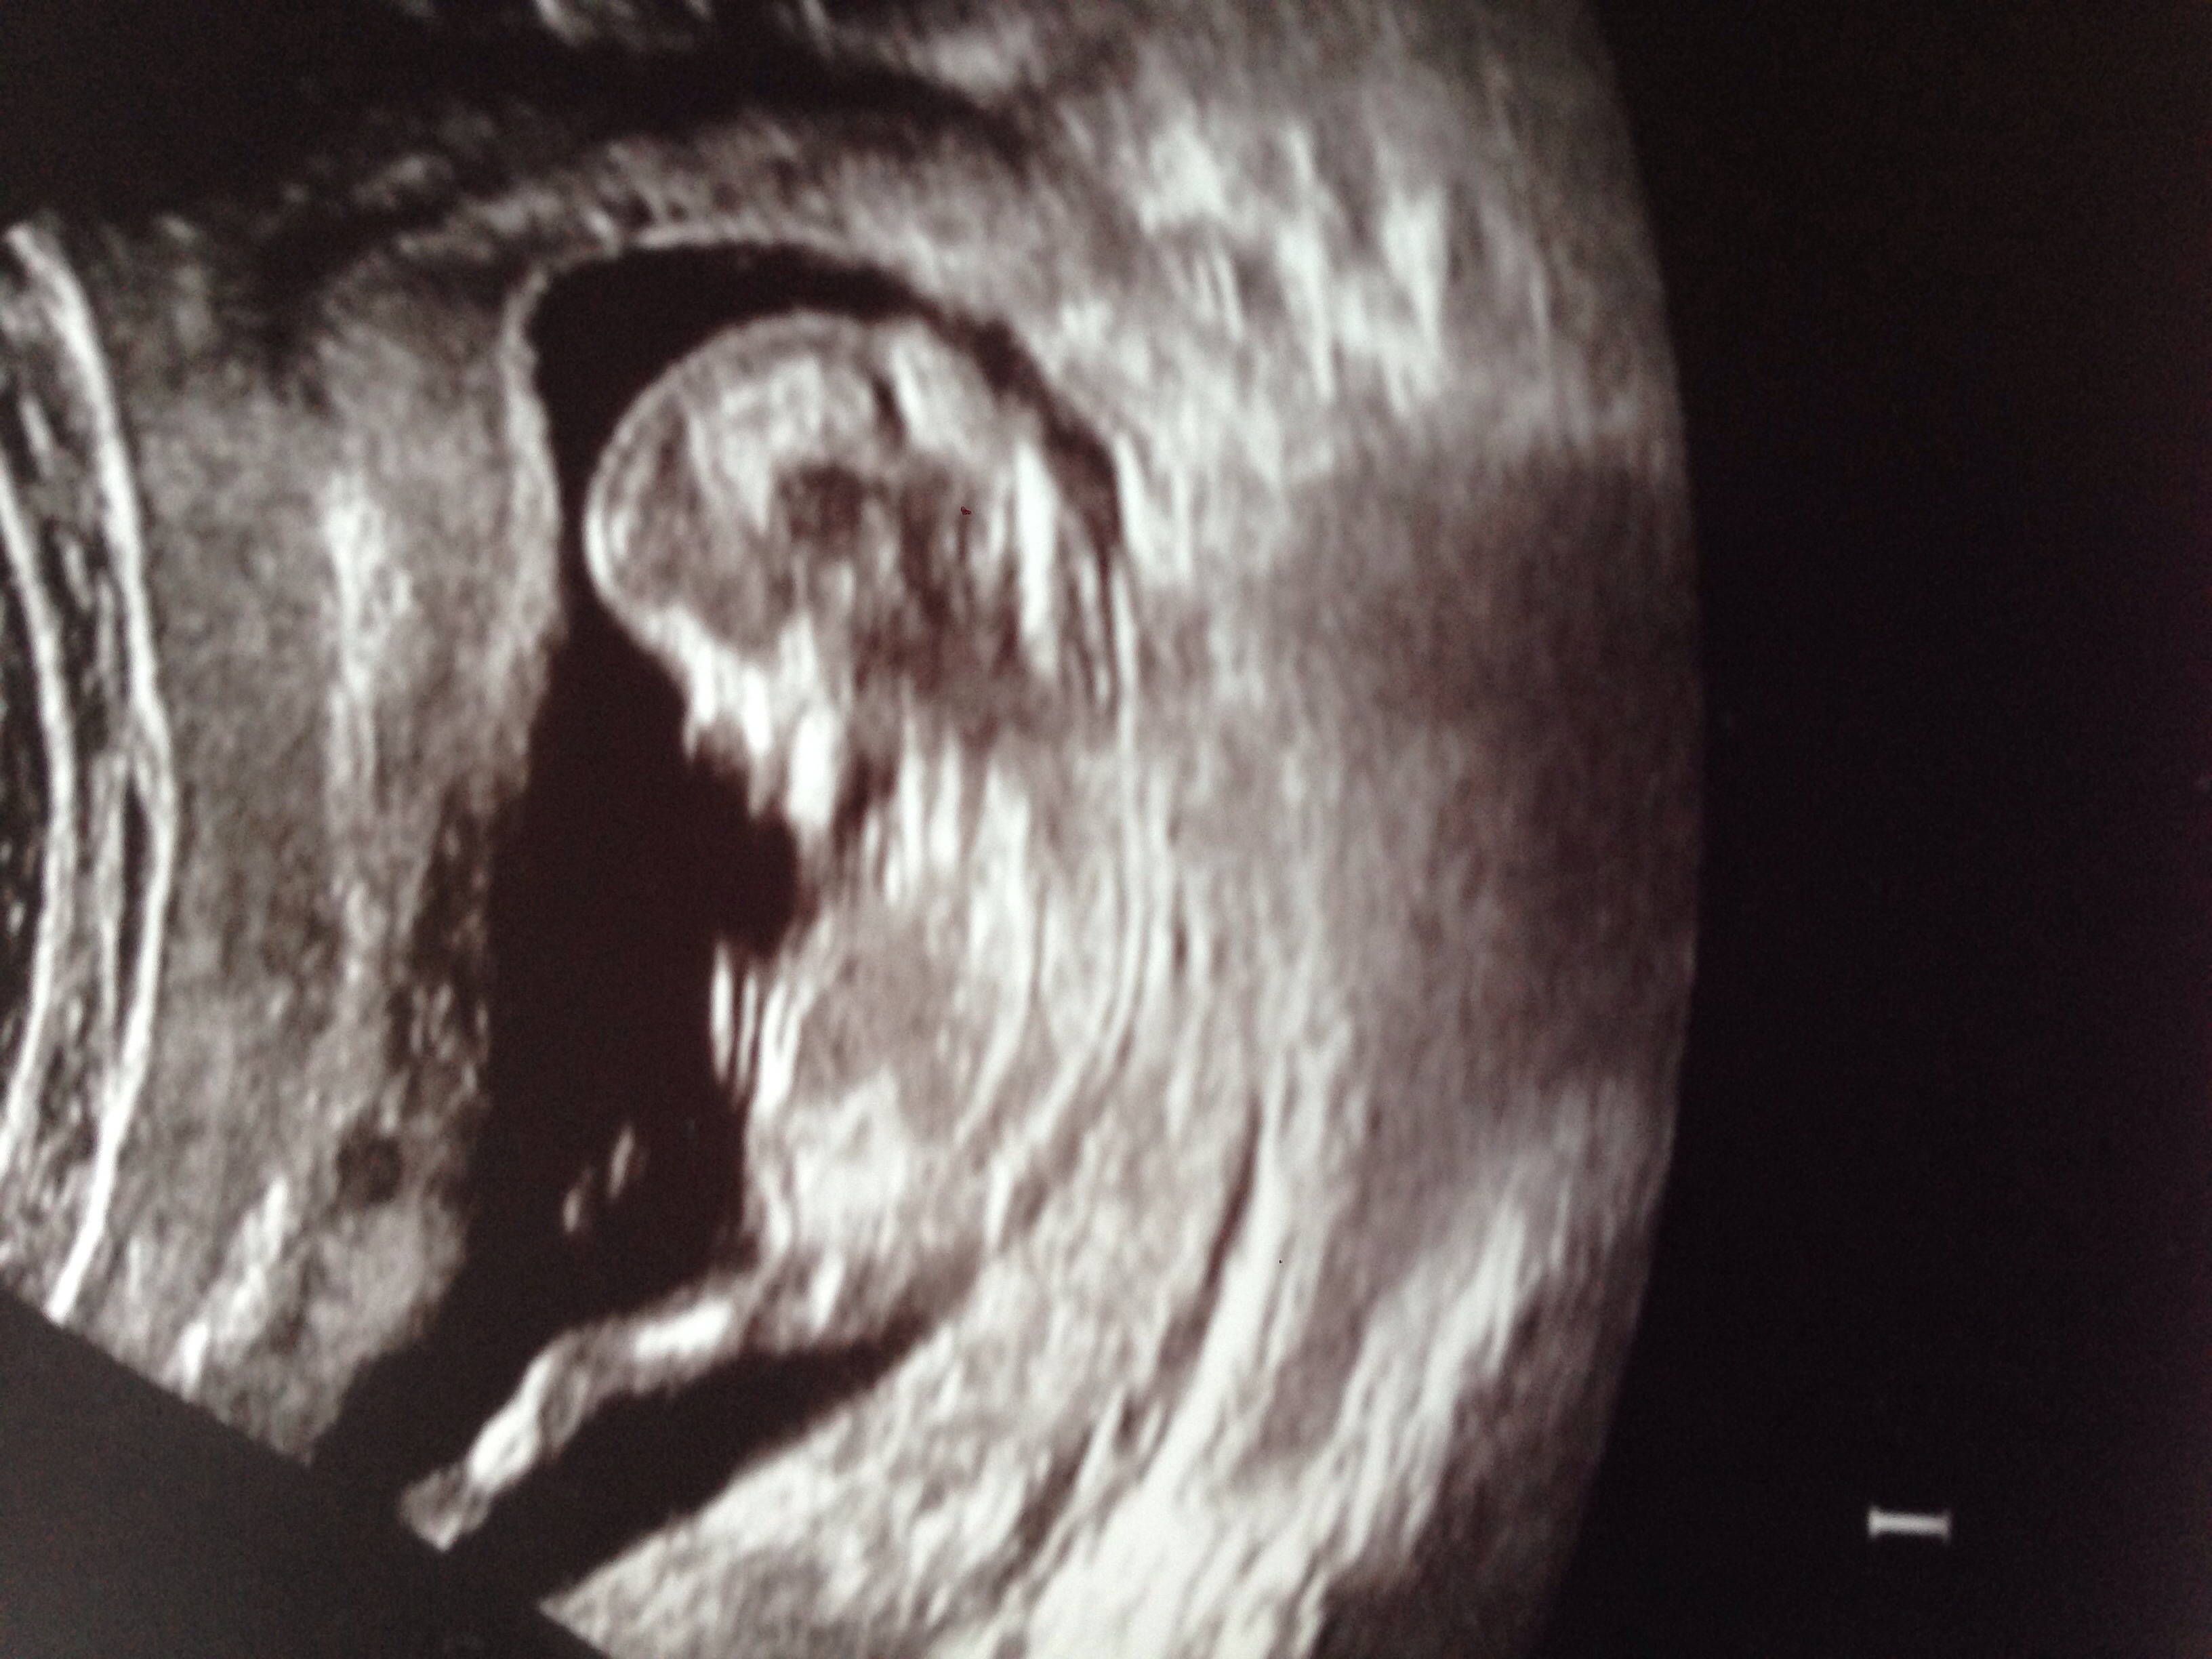

We had our NT scan today at 11w6d. Little bean did not want to cooperate at all so it took 50 minutes of the tech bouncing to probe on my belly and me coughing to get it to move into a position for her to do RE measurement. Little bean clearly takes after it's father in stubborness. We are doing the two sets of blood tests plus NT scan so we won't get our results for 5 weeks but our NT was 2.2mm which seems to be in the acceptable range according to doctor google.